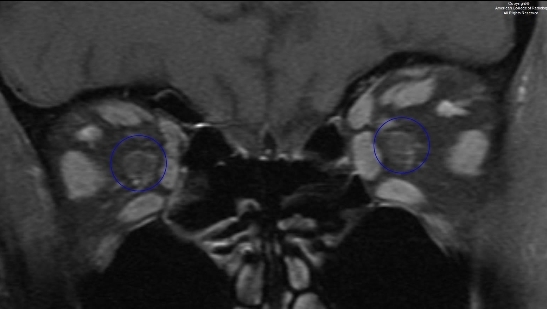

图 7 为冠状 T1 强化伴压脂序列示双侧视神经对称,未见异常强化(圈)